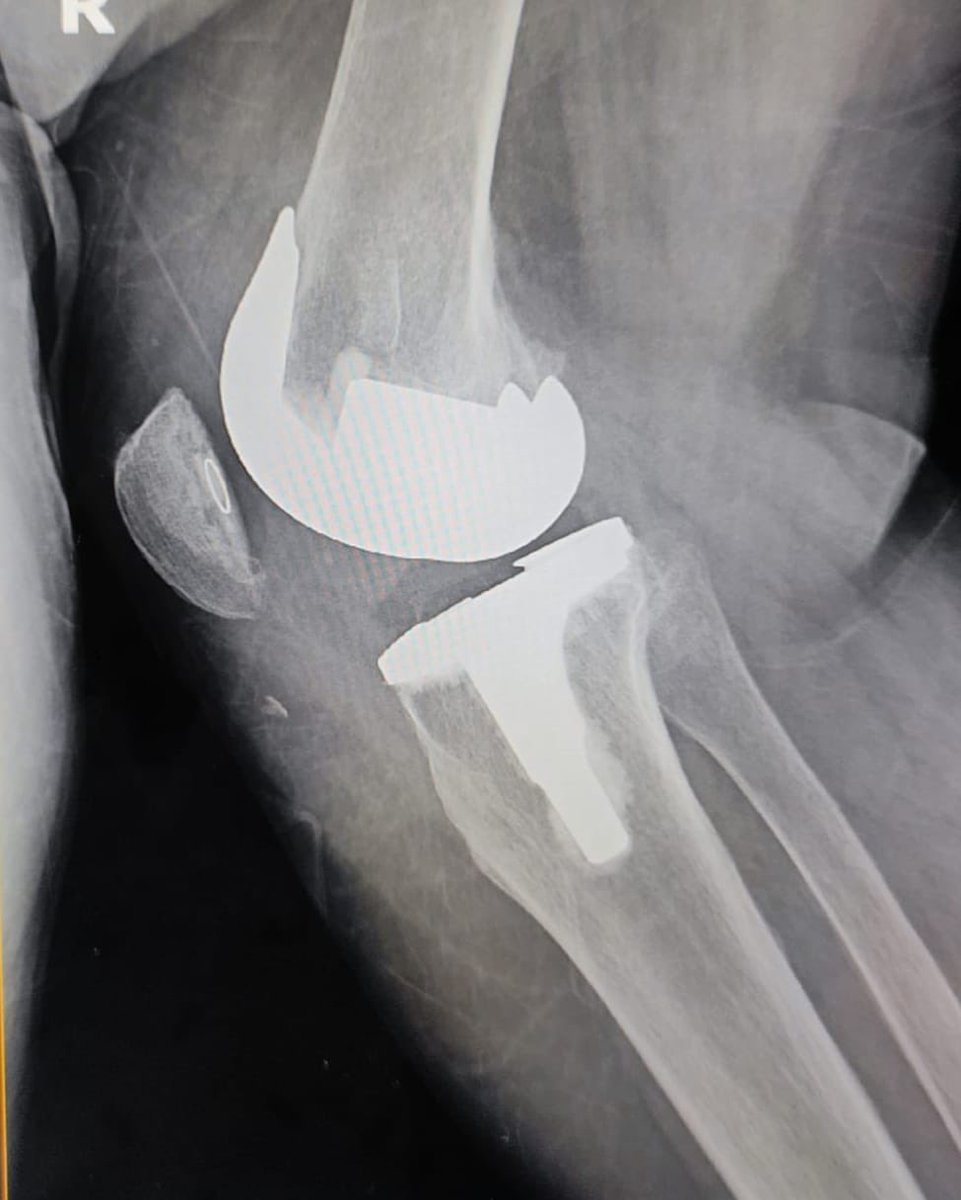

Her X Ray showed fracture inches above TKR

We did TKR for both her knees. She went back home in 4 days. Came back for follow up in a week completely able to walk by herself & also climbing stairs with some support.